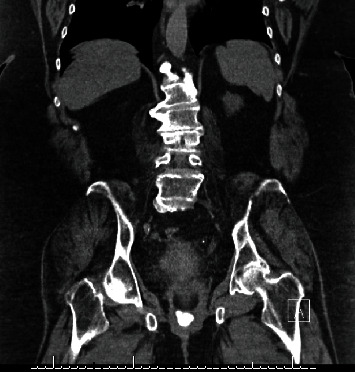

阴道结石是一种罕见的临床症状,可能在阴道尿液淤积的情况下出现。导致结石形成的因素有很多,结石的大小、位置和邻近结构的位置都会使处理变得复杂。一般来说,一旦确诊为阴道结石,应立即将其取出,并彻底评估周围的解剖结构,看是否有继发性瘘管、侵蚀或异物存在。本报告介绍了一例患有出血性膀胱炎的老年患者,其阴道结石形成于暴露的尿道中段吊带网片上。本报告强调了病理生理学、诊断因素和治疗方法。

The presence of a vaginal calculus is a rare clinical entity which may develop in the setting of vaginal urinary stagnation. Numerous factors contribute to stone formation, and management can be complicated by variations in size, location of the stone, and location of adjacent structures. Generally, once diagnosed, vaginal calculi should be removed and surrounding anatomy should be evaluated thoroughly for secondary fistula, erosion, or presence of an instituting foreign body. This report presents a case of vaginal calculus formation on exposed midurethral sling mesh in an elderly patient with hemorrhagic cystitis. This report emphasizes contributing pathophysiology, diagnostic factors, and treatment.